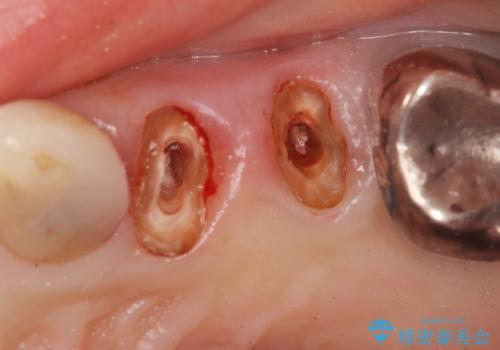

銀歯を除去したところ大臼歯は十分な歯質が残っていたため残すことができましたが、小臼歯の2本は虫歯の再発により残っている歯質が非常に少なく破折リスクが非常に高いと判断しました。

長期的な予後を見込むことが難しいため、相談の上抜去を行いインプラント治療を進めていくこととなりました。